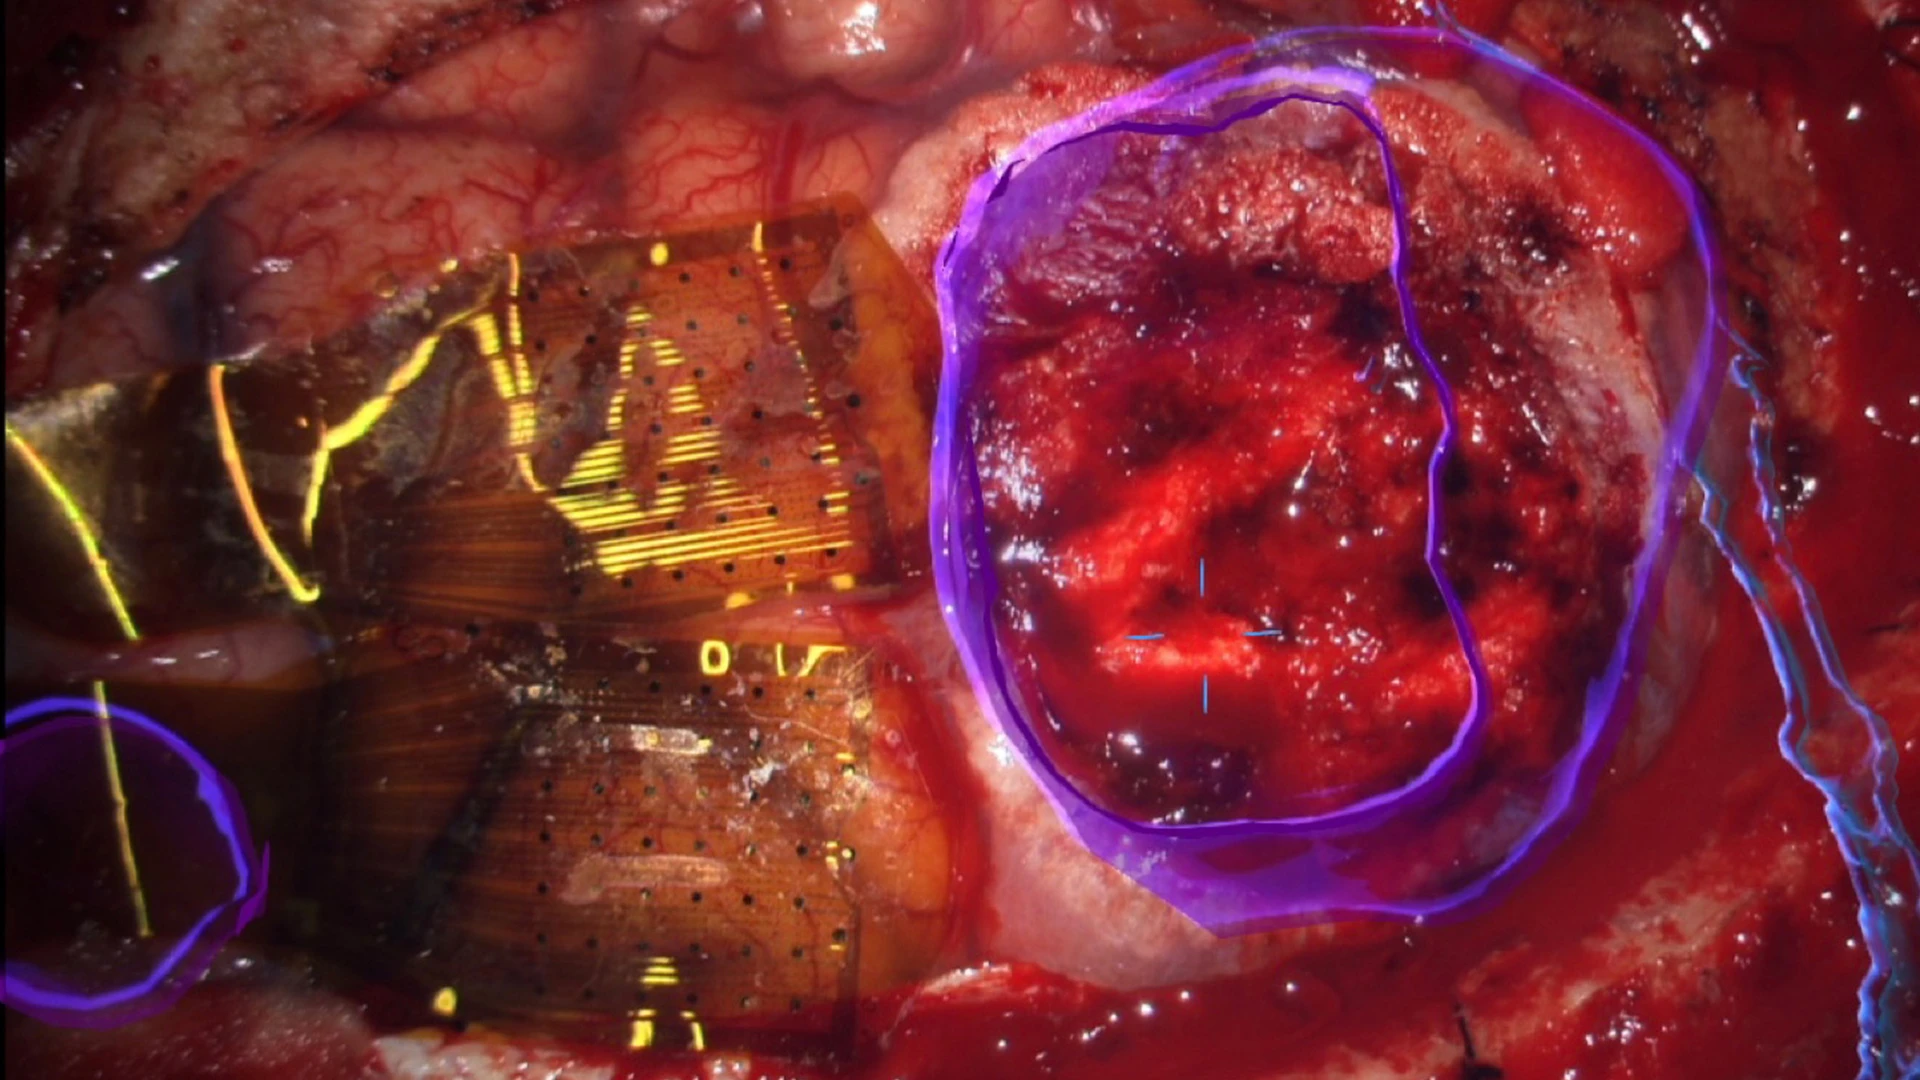

Figure 1. This composite figure illustrates intraoperative mapping of primary somatosensory cortex at high resolution using 2,048 surface microelectrodes.

Top Right. Operative field as seen through an operative microscope, with augmented reality overlay in blue to highlight the tumor, right. Two 1,024-electrode arrays, totaling 2,048 microelectrodes, are shown in position straddling the central sulcus, including the precentral (motor) and postcentral (somatosensory) gyri anterior to the tumor, left.

Bottom. Intraoperative setup including displays for frameless stereotactic neuronavigation, left; augmented reality overlay, 3D rendering of the operative field, and high-resolution electrocorticography by Precision Neuroscience, far right. Neurosurgeon Joshua B. Bederson, MD, is positioned at head of patient.